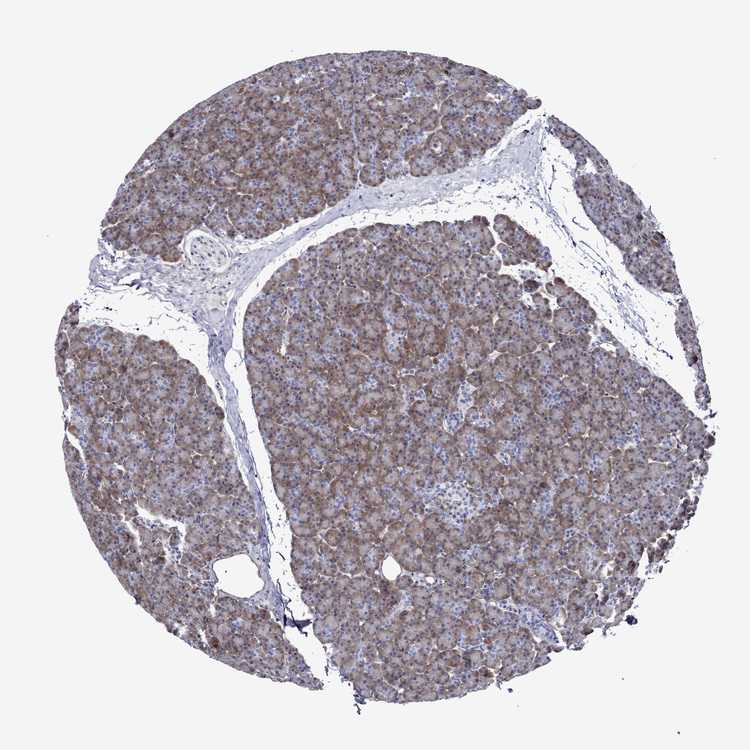

PANCREAS - Antibody stainingi

Antibody staining in the annotated cell types in the current human tissue is reported as not detected, low, medium, or high, based on conventional immunohistochemistry profiling in selected tissues. This score is based on the combination of the staining intensity and fraction of stained cells.

Each image is clickable and will lead to virtual microscopy that enables deeper exploration of all samples and also displays staining intensity scores, fraction scores and subcellular localization as well as patient and tissue information for each sample.

Antibody HPA018892Antibody HPA072690Antibody CAB009820Antibody CAB020718

Exocrine glandular cells LowMediumLowLow

Pancreatic endocrine cells MediumNot detectedLowNot detected